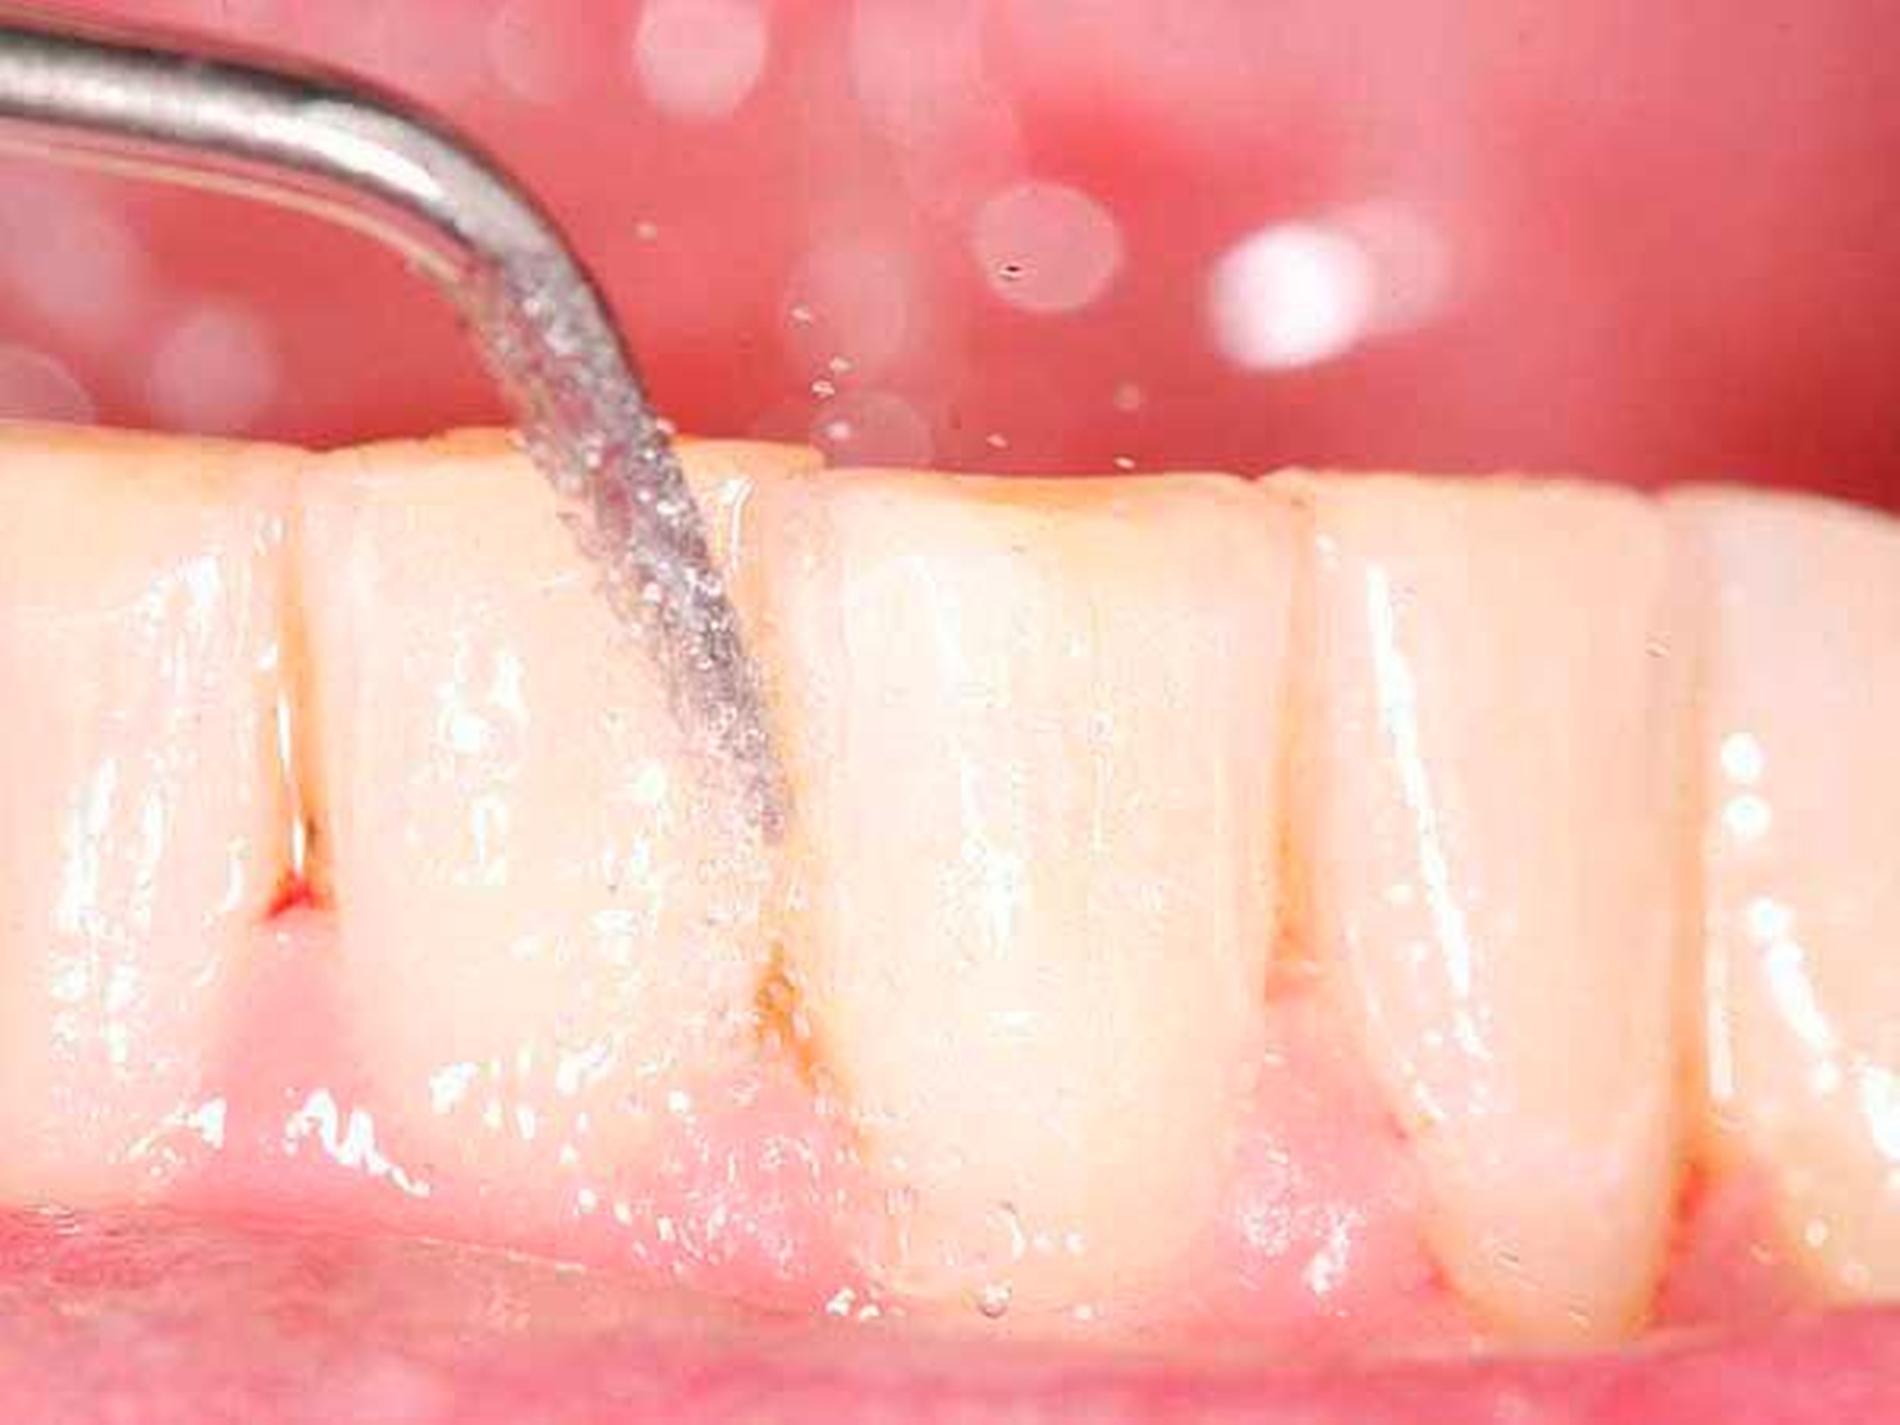

Für die subgingivale Instrumentierung kommen neben Handinstrumenten (wie Gracey-Küretten) auch maschinelle Instrumente mit Schall- oder Ultraschallantrieb infrage. In klinischen Studien zeigte eine Instrumentierung mit diesen Geräten keine deutlichen Unterschiede zwischen den verschiedenen Typen [Tunkel et al., 2002], zweckmäßigerweise können Hand- und maschinelle Instrumente kombiniert eingesetzt werden [Jepsen et al., 2011]. Eine übermäßige Bearbeitung der Wurzeloberflächen im Sinne einer klassischen Wurzelglättung sollte hierbei vermieden werden. Gleichzeitig ist eine Kürettage des Weichgewebes im Regelfall nicht indiziert [Heitz-Mayfield und Lang, 2013]. Neben einer seiten- oder quadrantenweisen Instrumentierung ist auch ein Full-Mouth-Scaling in einem Termin (oder an zwei Terminen innerhalb von 24 Stunden) möglich, allerdings ohne langfristig nachweisbaren klinischen Vorteil [Eberhard et al., 2015].

Von großem Interesse sind derzeit weiterhin subgingival eingesetzte Pulver-Wasserstrahl-Geräte. Mit gering abrasivem Pulver, häufig auf Glycin-Basis, können damit schnell und gründlich Biofilme, aber keine mineralisierten Ablagerungen entfernt werden [Flemmig et al., 2012]. Das Verfahren hat daher seine Stärke im Bereich der unterstützenden Parodontitistherapie, wo in der Regel keine ausgeprägten Konkremente zu erwarten sind. Für einen denkbaren Einsatz während der subgingivalen Instrumentierung liegen noch keine ausreichenden klinischen Daten vor, insbesondere ist wahrscheinlich die dem Verfahren immanente Gefahr eines Luftemphysems bei dem in der ersten Behandlungsphase oft noch stark aufgelockerten Gewebe (vgl. Abbildung 1) noch deutlich erhöht.